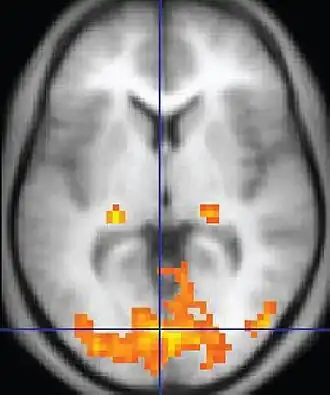

| Functional MRI (fMRI) | Blood-oxygen-level dependent imaging | BOLD | Changes in oxygen saturation-dependent magnetism of hemoglobin reflects tissue activity.[29] | Localizing brain activity from performing an assigned task (e.g. talking, moving fingers) before surgery, also used in research of cognition.[30] |

|

Functional MRI (fMRI) measures signal changes in the brain that are due to changing neural activity. It is used to understand how different parts of the brain respond to external stimuli or passive activity in a resting state, and has applications in behavioral and cognitive research, and in planning neurosurgery of eloquent brain areas.[48][49] Researchers use statistical methods to construct a 3-D parametric map of the brain indicating the regions of the cortex that demonstrate a significant change in activity in response to the task. Compared to anatomical T1W imaging, the brain is scanned at lower spatial resolution but at a higher temporal resolution (typically once every 2–3 seconds). Increases in neural activity cause changes in the MR signal via T*

2 changes;[50] this mechanism is referred to as the BOLD (blood-oxygen-level dependent) effect. Increased neural activity causes an increased demand for oxygen, and the vascular system actually overcompensates for this, increasing the amount of oxygenated hemoglobin relative to deoxygenated hemoglobin. Because deoxygenated hemoglobin attenuates the MR signal, the vascular response leads to a signal increase that is related to the neural activity. The precise nature of the relationship between neural activity and the BOLD signal is a subject of current research. The BOLD effect also allows for the generation of high resolution 3D maps of the venous vasculature within neural tissue.